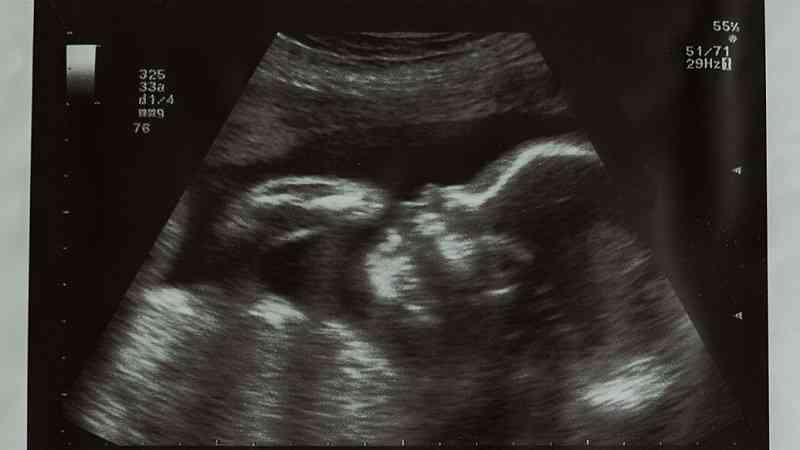

我今年26岁,9月19号因为输卵管双侧积水刚做完宫腹腔镜输卵管切除手术,手术过程中发现有宫腔黏连,最近几天感觉每次想大便之前肛门都有坠痛感,小腹右侧偶尔有阵痛,想我问问这种情况正常吗?